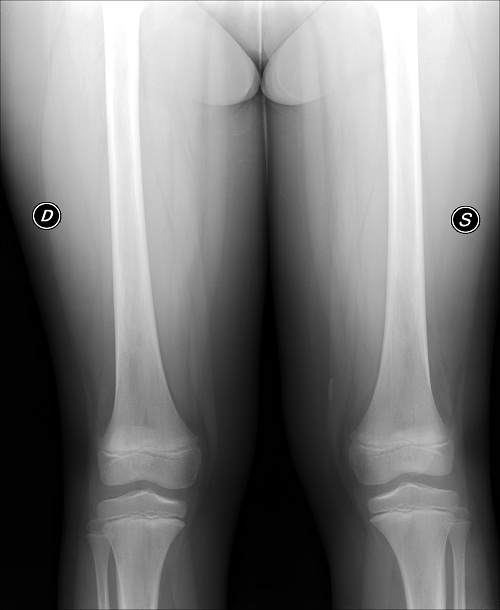

Negativa la radiografia delle sedi interessate dal dolore (Figura 1a), agli esami ematici enzimi muscolari nella norma e riscontro esclusivo di un incostante lieve rialzo degli indici di flogosi (PCR max 33 mg/l). All’emocromo GB 6.650 (N 52%, L 30%, M 11%), Hb 10,9 g/dl, MCV 63,5 fl, MCH 22,5 pg, RDW 15% e allo striscio periferico riscontro di un’anisocitosi con emazie a bersaglio. Reticolociti 26 per mille.

a. Rx femori eseguita in corso di crisi dolorosa ossea, negativa per alterazioni della diafania di corticale e midollare.